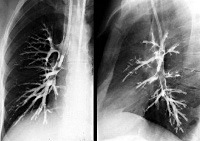

Рентгенография и КТ легких обнаруживает деструктивное поражение легких, деформацию бронхов, участки гиповентиляции и ателектаза. Вторичные изменения бронхов (стенозы, бронхоэктазы) выявляются в процессе бронхографии. Фибробронхоскопия позволяет установить локализацию и форму процесса: катаральный эндобронхит, инфильтративное, язвенное, рубцовое поражение слизистой, фистулу бронха. Однако даже отсутствие эндоскопических признаков специфического поражения не исключает диагноза туберкулеза бронхов. Подтвердить факт бактериовыделения позволяет исследование мокроты и лаважной жидкости на наличие МБТ.